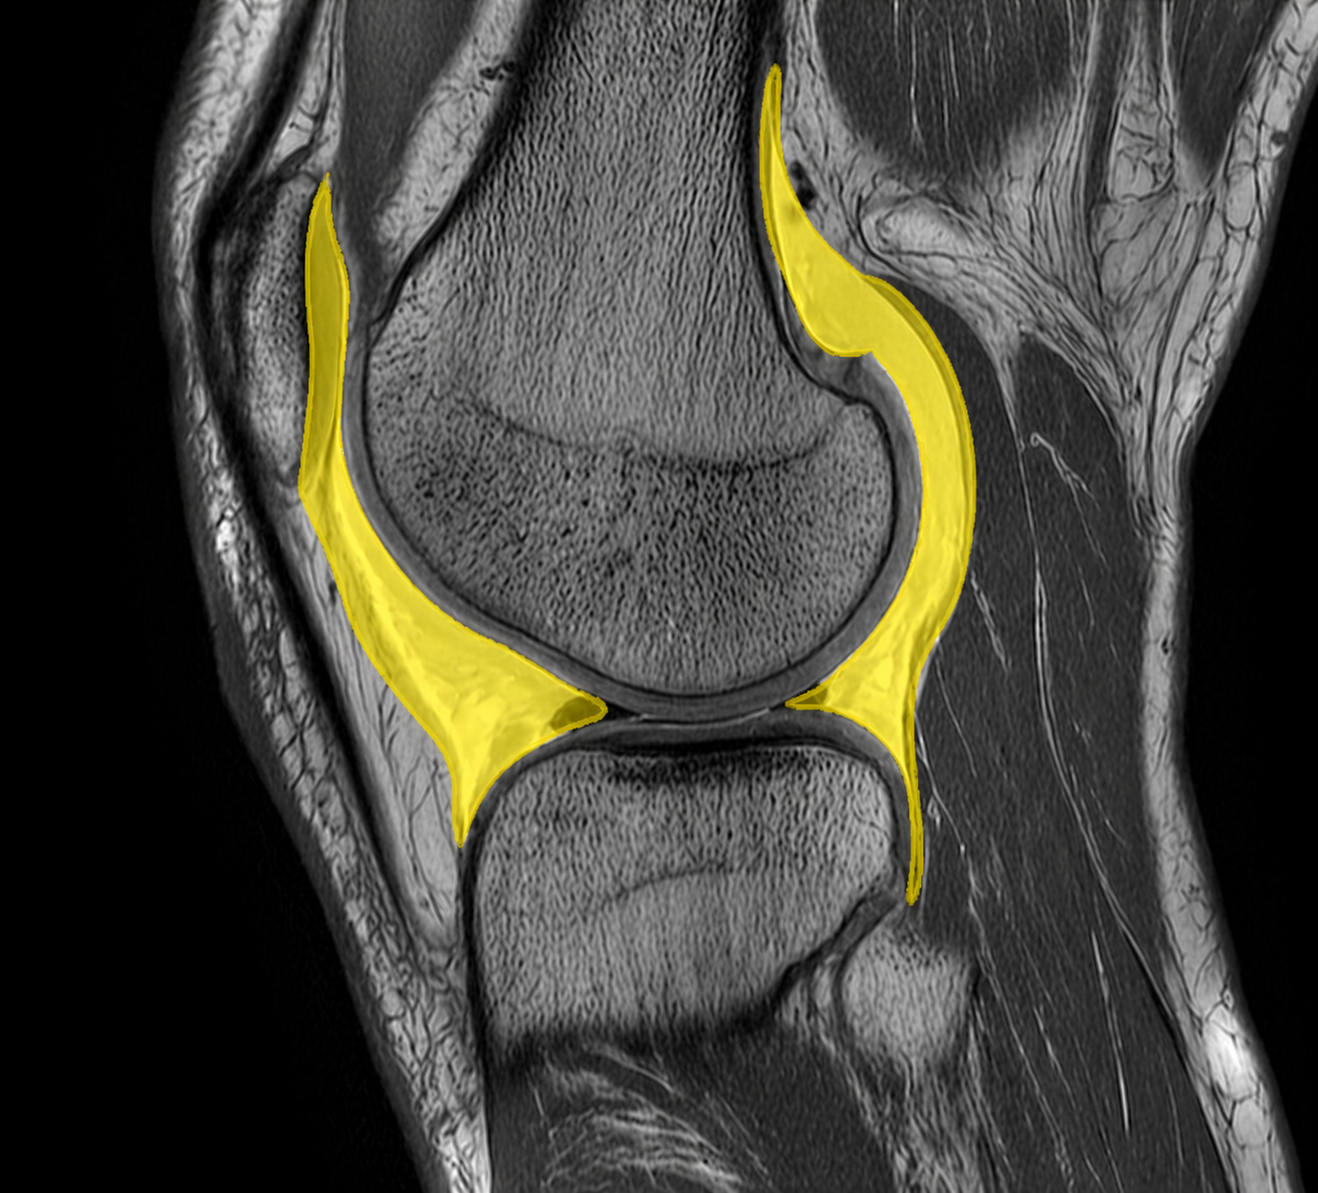

MR-bild av knäled där ledvätska (hydrops) är markerad i gult. Vätskeansamlingen ses intraartikulärt och följer ledkapseln runt femurkondylen och tibia, vilket är typiskt vid inflammation, trauma eller annan intraartikulär irritation.

På MR ses vätska som en högsignal i vätskekänsliga sekvenser (t.ex. T2-viktade bilder), vilket gör det möjligt att skilja normal mängd från patologisk vätskeansamling. Samtidigt kan man bedöma om det finns tecken på synovit, kapselpåverkan eller andra reaktiva förändringar.